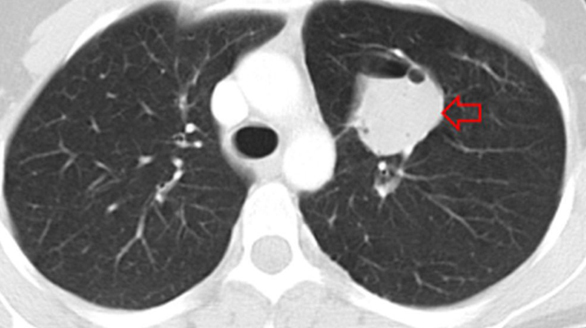

Congenital Lung Malformations

Bronchogenic/Foregut Duplication Cysts

Mediastinal and Lung Tumors

Hydatid Disease of Lung